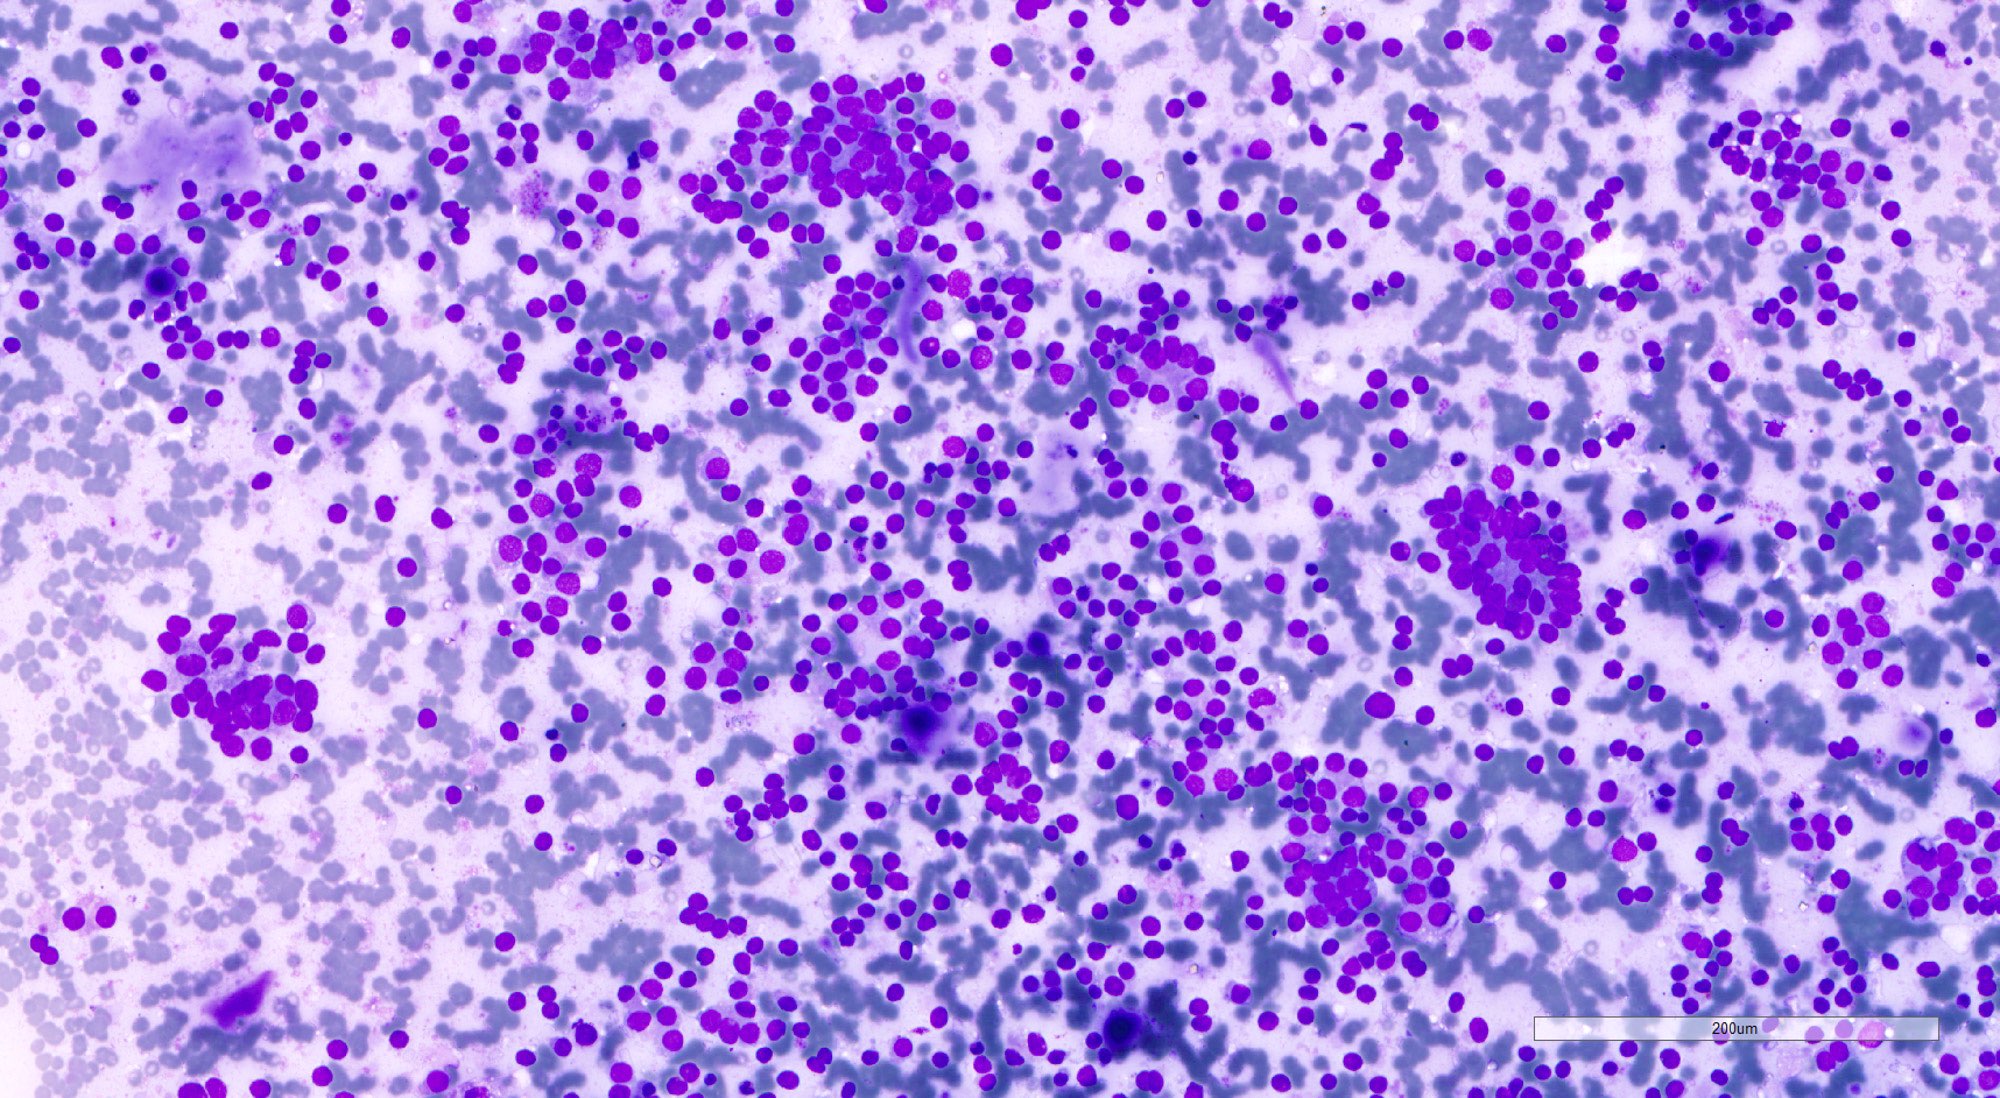

Cytology description

- Cellular aspirate (Korean J Pathol 2013;47:61, J Pathol Transl Med 2018;52:110)

- Cellular crowding

- Variable number of singly dispersed cells

- Microfollicular and solid / trabecular variants: numerous microfollicles, may have scant luminal colloid; absent or minimal background colloid

- Normofollicular and macrofollicular variants: monolayer sheets of follicular cells, abundant colloid; may mimic benign follicular nodule

- Hyperfunctioning follicular adenoma and follicular adenoma with papillary hyperplasia: monolayer sheets of polygonal cells with abundant cytoplasm, flame cells and occasionally, papillary fragments

- Uniform small round to ovoid nuclei, smooth nuclear margin, fine nuclear chromatin

- Absent nuclear features of papillary thyroid carcinoma

- The Bethesda System for Reporting Thyroid Cytopathology (TBSRTC) IV (follicular neoplasm / suspicious for a follicular neoplasm [FN / SFN]), III (atypia of undetermined significance [AUS A]) or II (benign) (Thyroid 2017;27:1341, Clin Endocrinol (Oxf) 2018;88:936)

- Cannot rule out follicular thyroid carcinoma based on cytologic findings

Cytology images